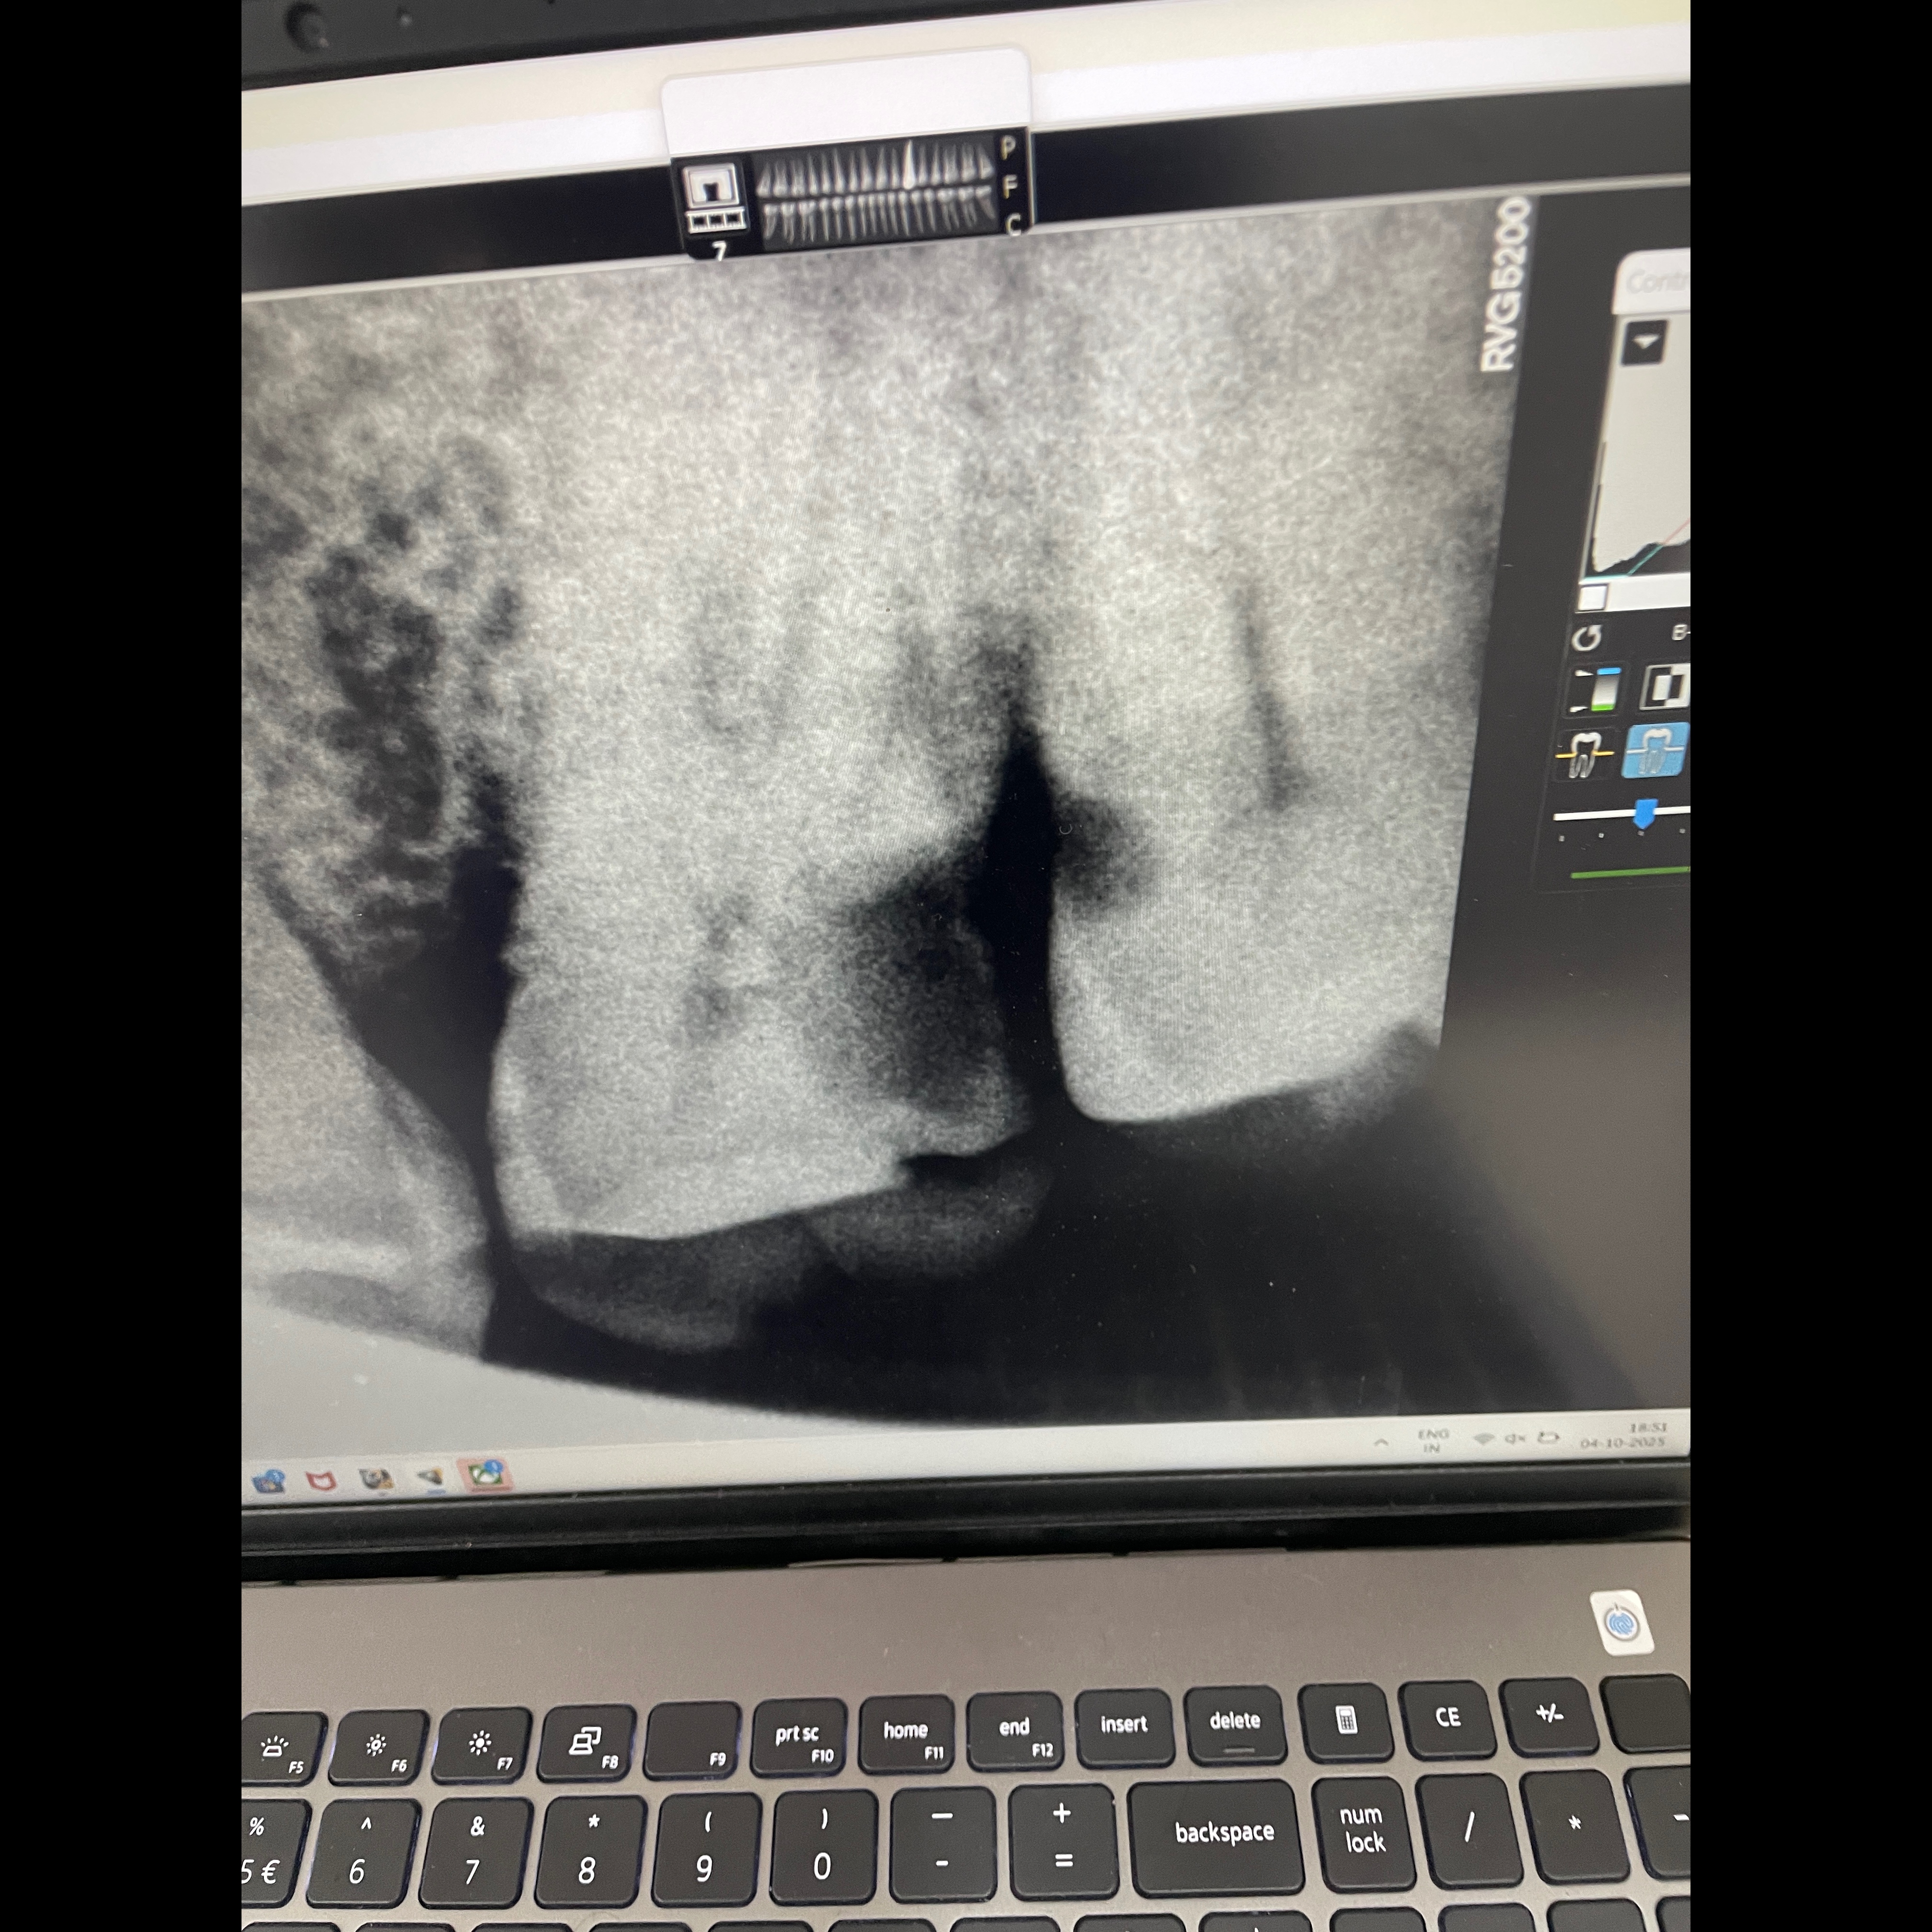

Why remove when you can restore? Experience gentle and advanced Root Canal Treatment at Dhaanya’s Dental — where your comfort and smile come first! Toothache troubling you? It might not need extraction! At Dhaanya’s Dental, our advanced Root Canal Treatment saves your natural tooth — painlessly and efficiently. ✨ Relief. Restoration. Renewal. 📍 Mogappair West, Nolambur Painless Precision Save Your Smile Expert Hands, Gentle Care Advanced RCT Technology Relief in One Sitting Your Tooth, Our Care